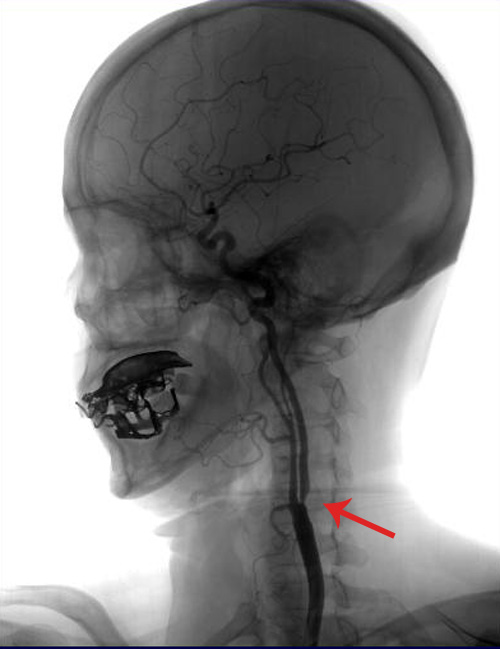

彩色多普勒超声(2011-3-17,外院):双侧颈动脉内膜增厚伴斑块形成(多发),左侧颈动脉球部狭窄(70-99%),双侧椎动脉椎间隙段、颈段走行弯曲,右侧锁骨下动脉内膜增厚。

TCD:左侧半球血流呈低流速低搏动性改变——左侧颈内动脉颅外段病变;左侧颈内-外侧枝开放;脑动脉硬化血流频谱改变;左侧椎动脉痉挛。

该患者左侧颈动脉球部狭窄(70-99%),症状明显,符合颈动脉内膜剥脱术手术指征。2011年3月25日,由协作组张勤奕教授顺利为其实施了左侧颈动脉内膜剥脱术。